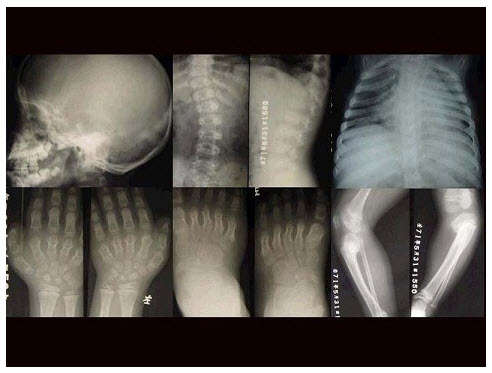

100、单项选择题

女,3岁,身体发育异常,如图所示,最可能的诊断为()

A.成骨不全

B.粘多糖病

C.软骨发育不全

D.佝偻病

E.侏儒症